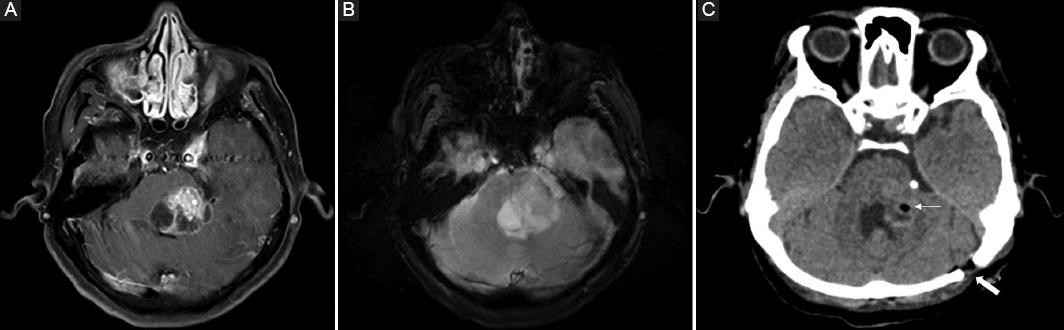

Figure 1 Brain magnetic resonance imaging (MRI) in axial sections, contrast-enhanced T1-weighted sequence, in which a heterogeneous image is observed at pontine level with intense enhancement to gadolinium in its solid portion, associated with hypointense areas suggestive of necrosis (A), while in T2-weighted sequence shows similar heterogeneity and irregular borders (B), whose histopathological diagnosis was Grade IV astrocytoma. Post-surgical head simple computed tomography (CT) demonstrates the biopsy site (thin arrow) and the burr-hole (thick arrow) (C).